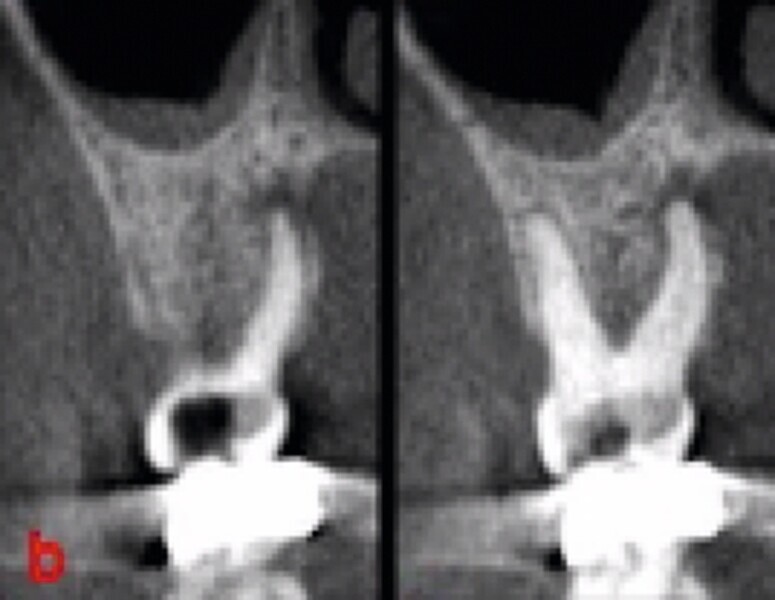

Fig. 34 : Radiographie de contrôle à deux mois.

La crête alvéolaire au niveau du site de la molaire inférieure était trop étroite pour permettre la pose prédictible d’un implant sans une augmentation osseuse préalable. Des implants deux pièces en zircone ont été mis en place, simultanément à une augmentation osseuse latérale, au moyen d’une allogreffe et d’une membrane de collagène résorbable (Figs. 25–34).